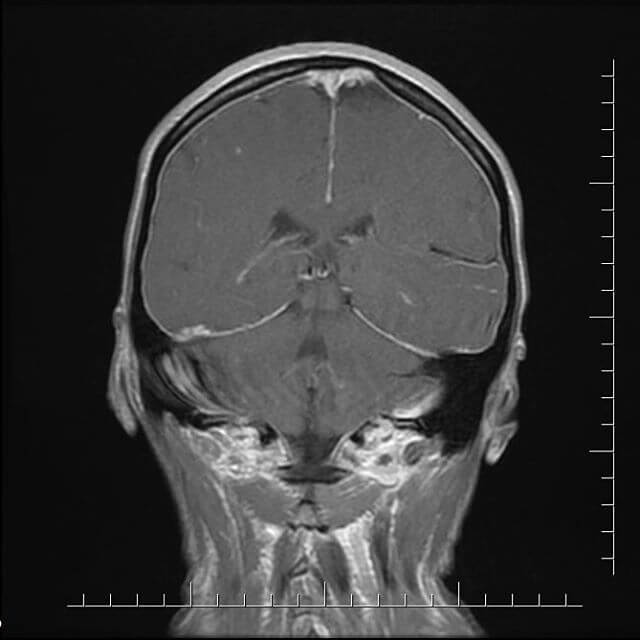

- МРТ.

- КТ.

- делают МРТ;

Установить правильный диагноз поможет офтальмолог при обследовании глазного дна. Расширение и извилистость вен глазного дна – довольно точный признак повышения внутричерепного давления. Ультразвуковое исследование позволяет определить степень нарушения оттока крови от тканей мозга. В сложных случаях необходима компьютерная томограмма. При принятии обезболивающих препаратов происходит снятие симптома, т.е. боли, но не уменьшение внутричерепного давления. Если длительно и неправильно лечить – существует угроза инсульта. Если внутричерепная гипертензия развивается у маленьких детей – это чревато водянкой мозга и увеличением размера головы.